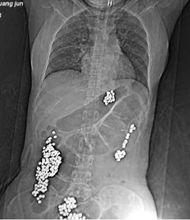

黃珺X光片醫生在《死亡醫學證明書》“死亡原因”一欄寫道:腸梗阻致大量胃內容物返流窒息。解放軍第一一三醫院高壓氧科主任蔣功達13日說,黃珺的死與較多金屬物堵住腸道有非常重要的關係。從入院開始,黃珺一直被警方銬在床上,處於平躺狀態,這導致堵在升結腸處的金屬物無法往外排,同時嘔吐的胃內容物返流。

在醫院救治時,通過CT檢查,發現黃珺體內有金屬物。經調查,金屬物為打火機機芯,與其用於自縊的彩燈項鍊線,均為在押人員在監房勞動的產品配件。